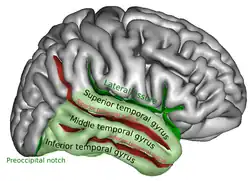

Cerebrum. Lateral view. Deep dissection. Superior temporal gyrus is visible at the center. | |

Position of superior temporal gyrus (shown in red).

Position of superior temporal gyrus (shown in red). Lateral view of a human brain, main gyri labeled.